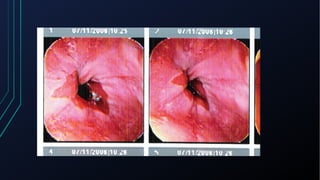

Dor torácica pode ter diversas causas, incluindo cardíacas como síndrome coronariana aguda, dissecção de aorta e pericardite, e não cardíacas como problemas pulmonares, musculoesqueléticos e do trato gastrointestinal. É importante avaliar a história clínica, características da dor e exame físico para identificar a possível causa e orientar o tratamento adequado.